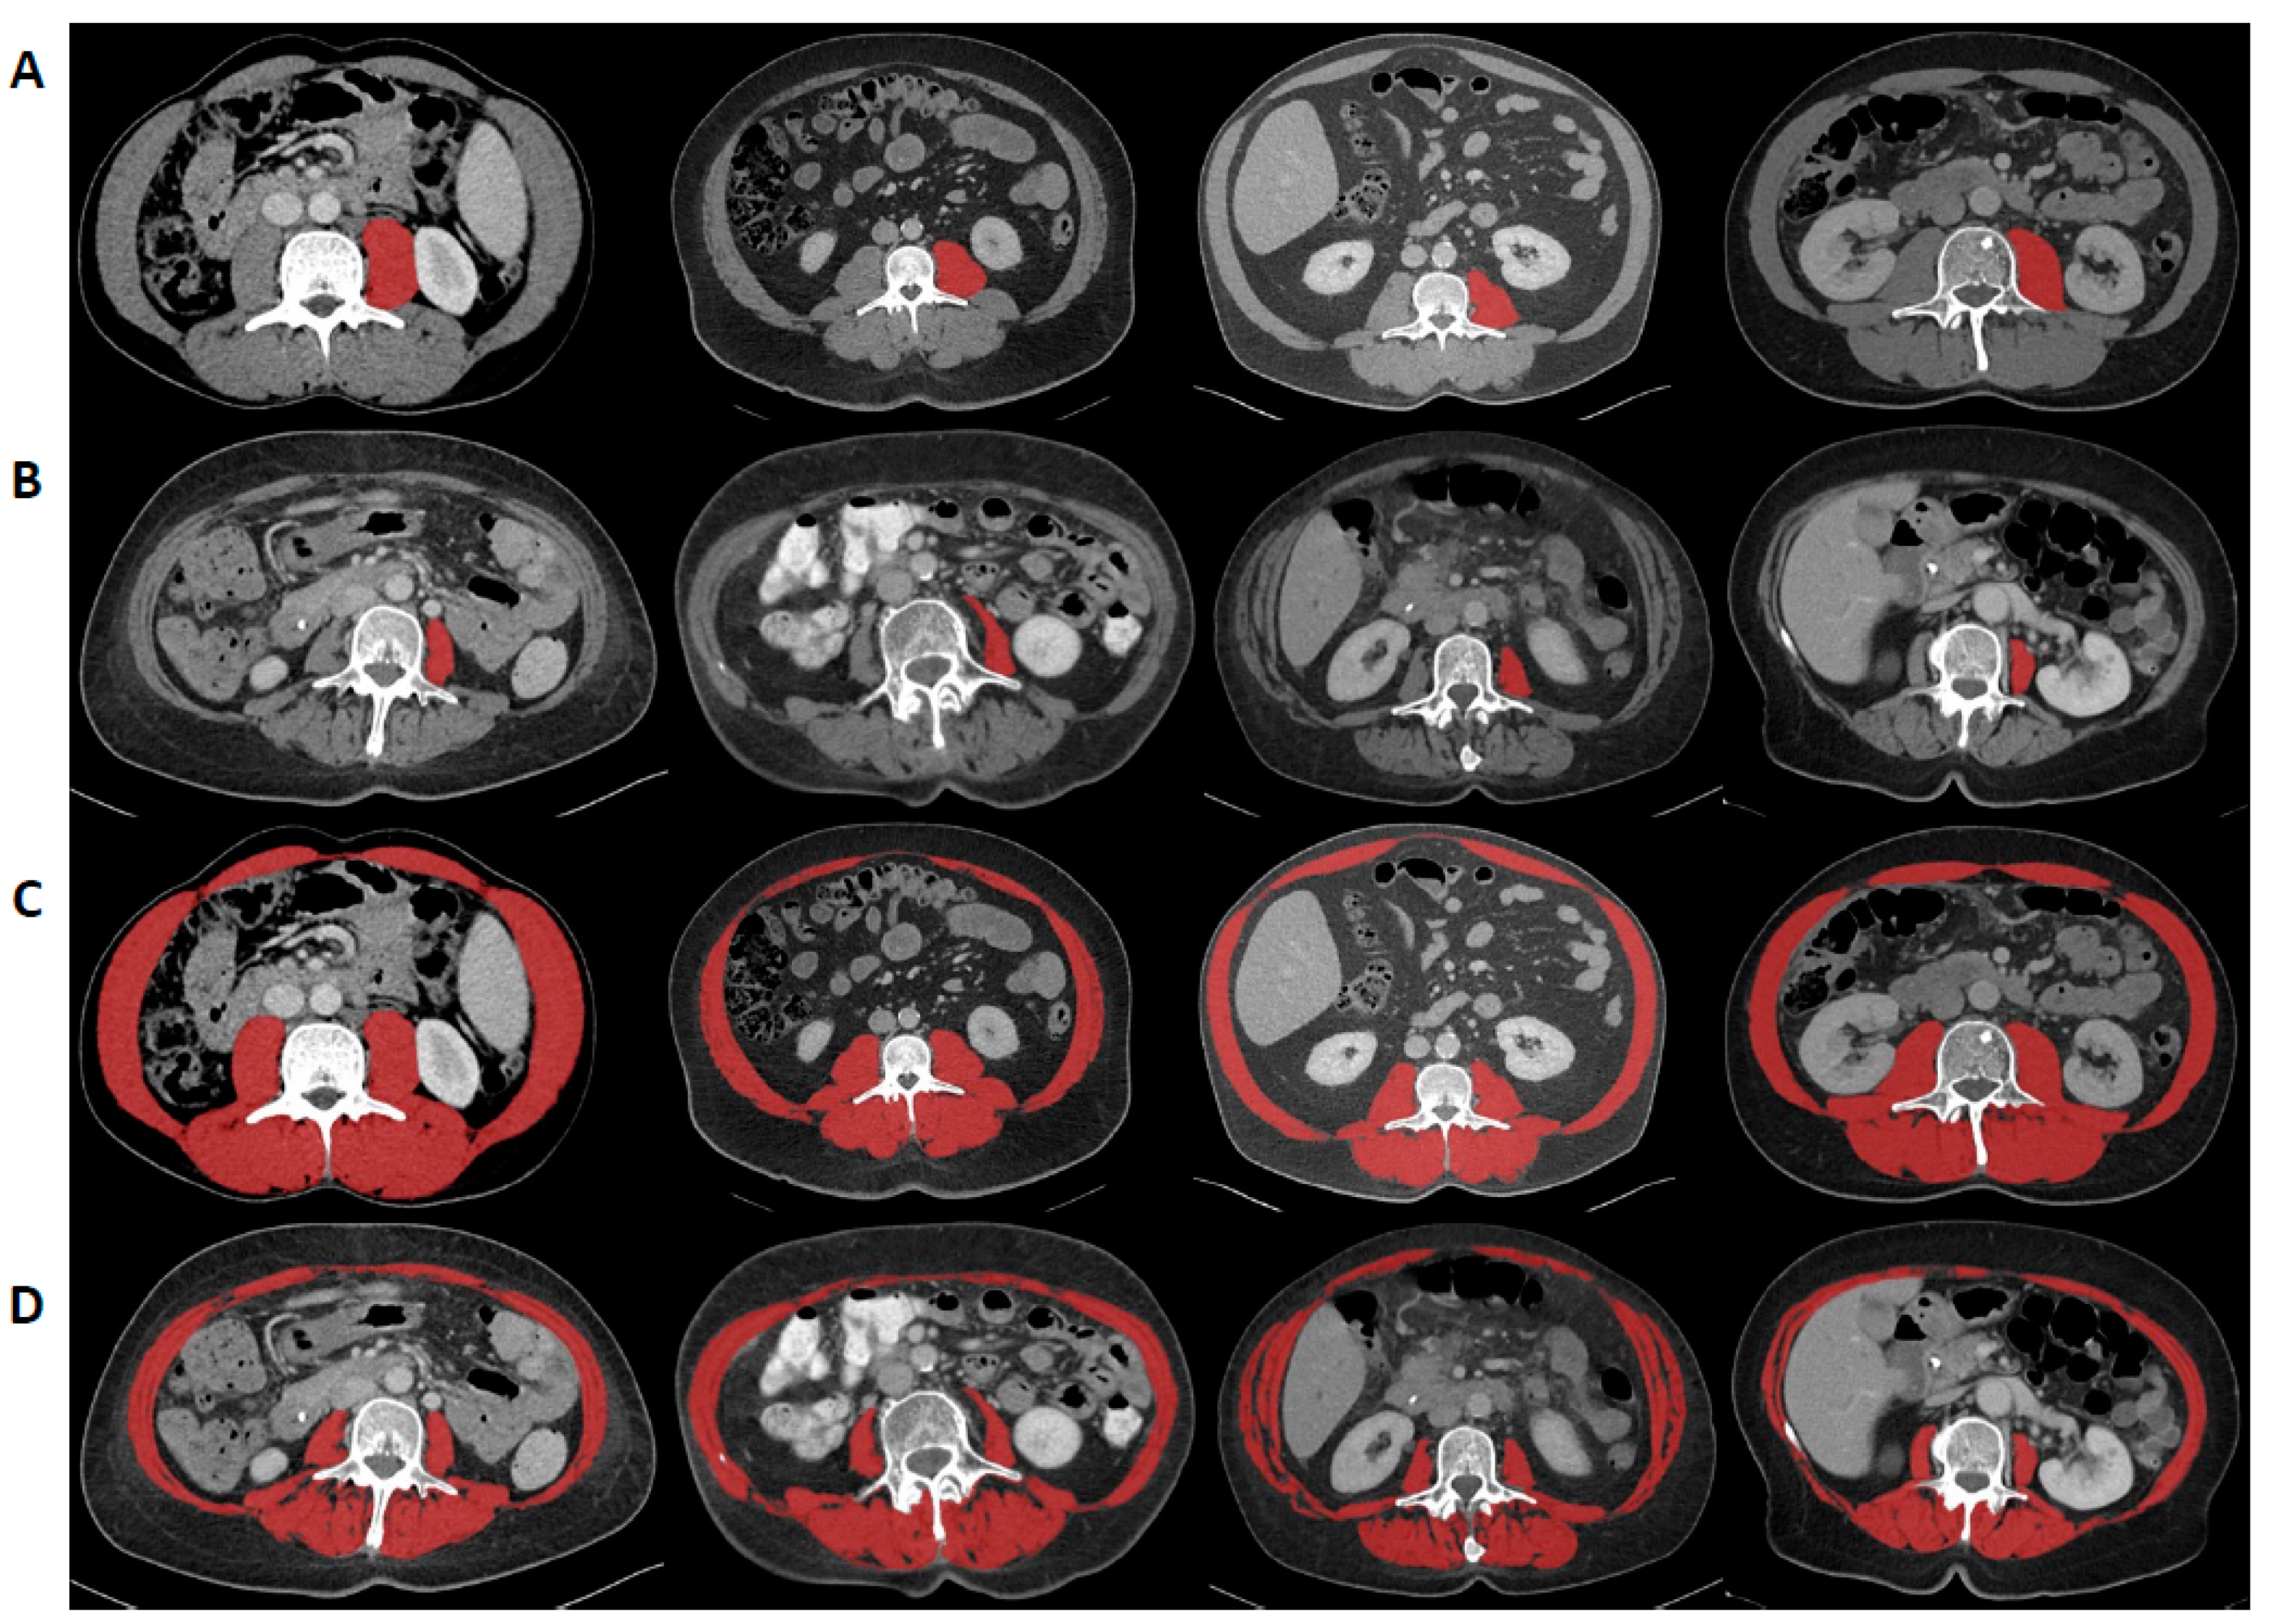

2.2. Analysis of Sarcopenia